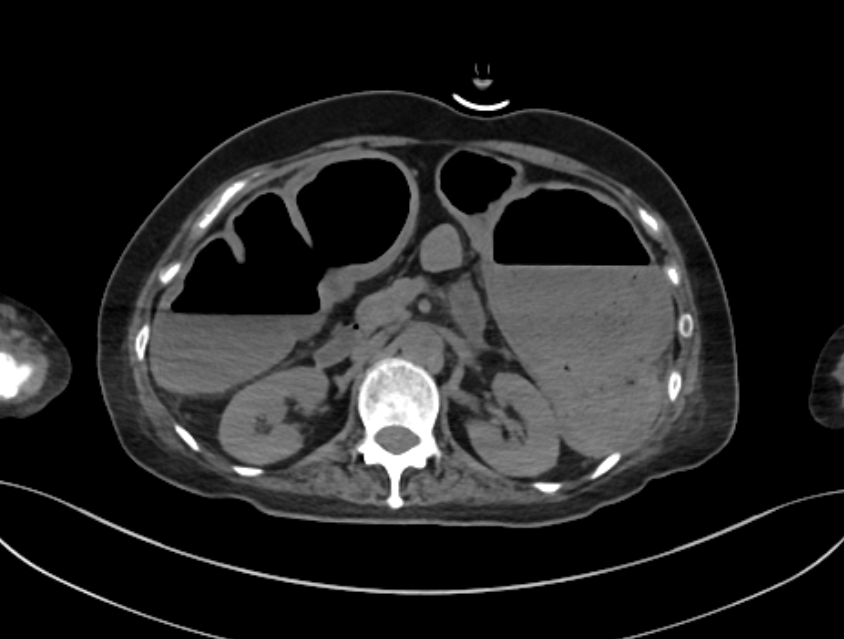

| CT | 장벽 비후, 염증 확산, 청공 여부 확인 |